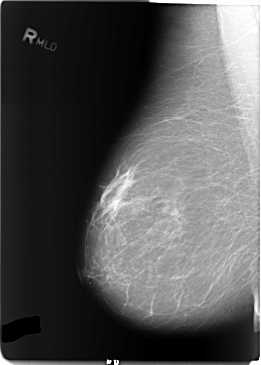

B_3122_1.RIGHT_MLO

RIGHT_CC LINES 5768 PIXELS_PER_LINE 4128 BITS_PER_PIXEL 12 RESOLUTION 50 NON_OVERLAY

RIGHT_MLO LINES 5832 PIXELS_PER_LINE 4168 BITS_PER_PIXEL 12 RESOLUTION 50 NON_OVERLAY